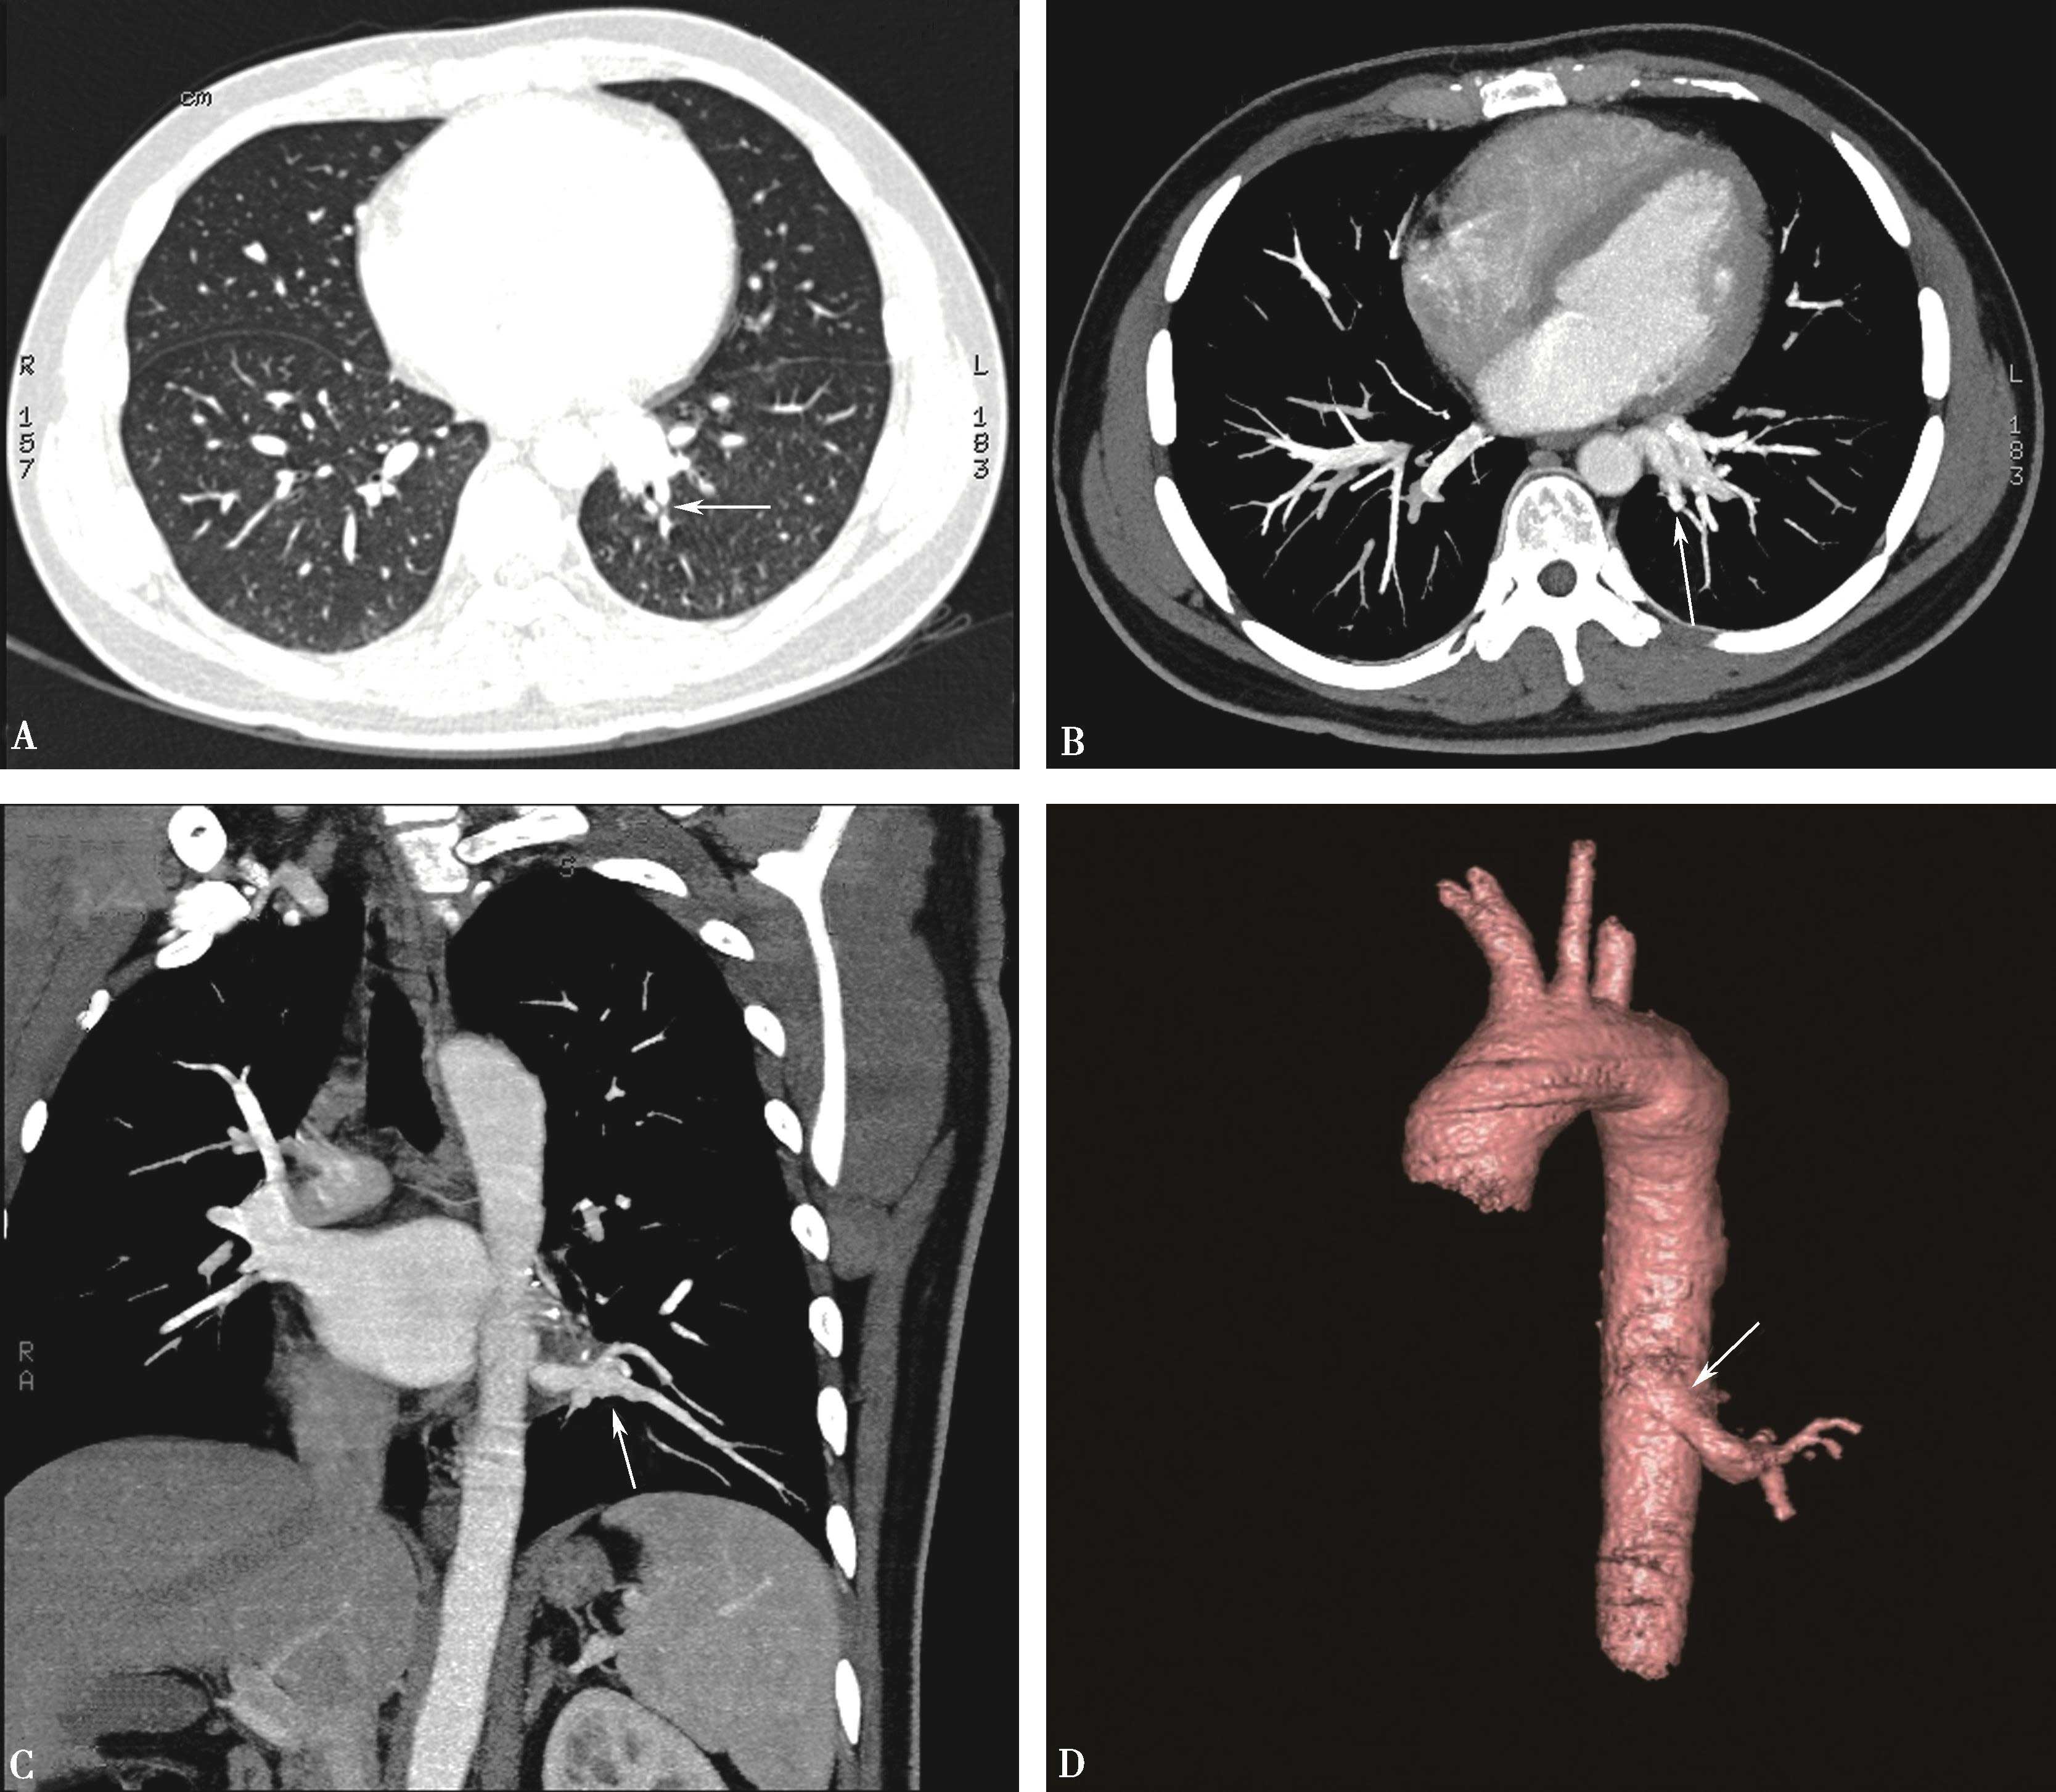

5.扫描采用对比剂智能自动跟踪触发技术,监测层面设定在气管分叉平面,ROI定位于肺动脉干,触发阈值定义为100Hu(图8-1-3,图8-1-4)。

(二)双期扫描法(图8-1-5)

图8-1-3 对比剂智能自动跟踪触发技术

造影剂智能自动跟踪触发技术能够准确获得扫描启动时间点并及时启动扫描

图8-1-4 常规肺动脉CT造影横断图及重建图像

图8-1-5 CTPA两期扫描应用:患者,男,37岁,二尖瓣狭窄,肺循环高压,怀疑肺栓塞。第一期右肺下叶基底段对比剂充盈不充分(ABC↑);第二期充盈充分(DEF↑),排除肺栓塞诊断